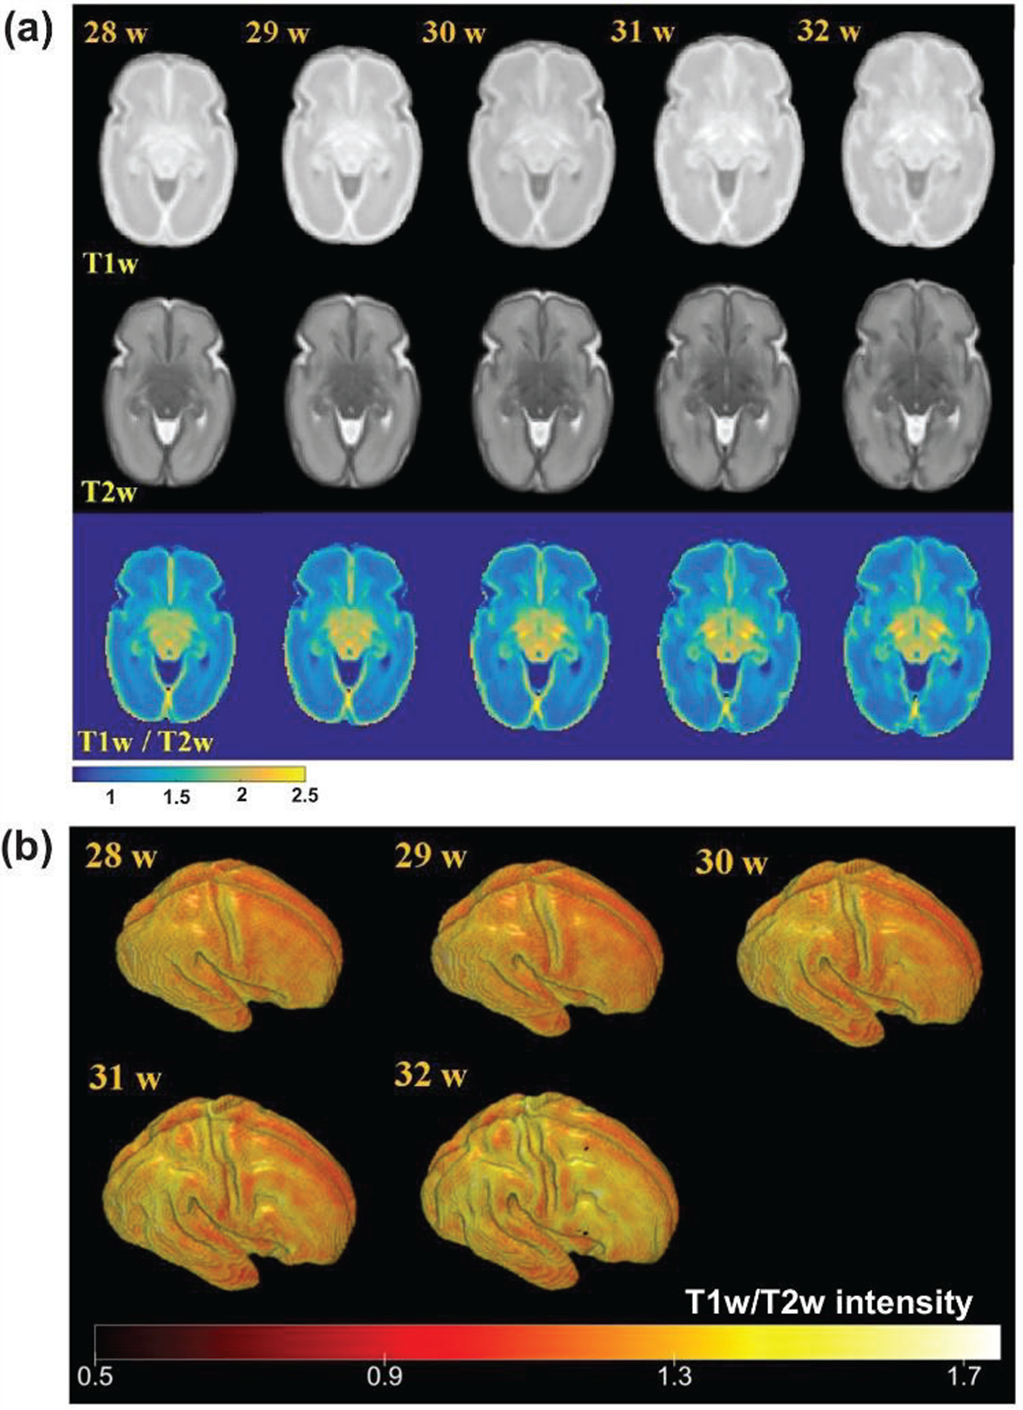

به گزارش روابط عمومی دانشگاه؛ دکتر حمید ابریشمی مقدم (مجری طرح) در خصوص تعیین پروفایل بالیدگی ساختار پری سیلوین بیان نمود: تشخیص مشکلات عملکردی مغز در مراحل مختلف رشد و در سریعترین زمان ممکن بسیار مهم است. از آنجا که ویژگیهای ساختاری مناسب به ‌عنوان نشانگرهای زیستی پیش‌بینی‌کننده می‌توانند مشکلات عملکردی را به طور زود هنگام مشخص کنند؛ در مطالعات مربوط به مغز و عملکرد آن، تعیین ارتباط بین ساختار مغز و عملکرد آن توجه زیادی به خود جلب کرده است. اطلس های ساختاری-عملکردی، که رشد نرمال مغز را مدل می­کنند، می‌توانند برای پیش بینی مشکلات عملکردی مغز ابزار مناسب و مؤثری باشند.

عضو هیات علمی دانشگاه صنعتی خواجه نصیرالدین طوسی افزود: یکی از بازه‌های مهم برای چنین مطالعه‌ای، دوران نوزادی است که در این بازه برای مطالعة عملکرد مغز یکی از مناسب‌ترین تحریکات که نیاز به همکاری نوزاد ندارد تحریک شنیداری است. از طرفی از مهمترین نواحی درگیر در تحریک شنیداری و زبان، به‌عنوان یکی از پیچیده‌ترین عملکردهای مهم اجتماعی و شناختی که از مراحل اولیة زندگی وجود داشته و در حال تکامل است، ناحیة پریسیلوین است که این پروژه روی این ناحیه متمرکز می‌باشد. ویژگی‌های ساختاری که از این ناحیه استخراج می­شود؛ باید تغییرات مورفولوژیکال مربوط به رشد را مدل کند و همچنین با ویژگی‌های رشد عملکردی ارتباط داشته باشد و بنابراین در ارائة مدل پروفایل رشد عصبی کارآمد باشد.